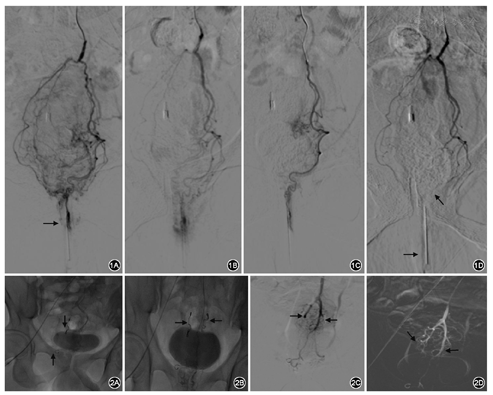

所有患者术前均经结肠镜、肛门指检、电子肛直肠镜、心电图、出凝血和血常规等检查,用开塞露进行肠道准备,电子肛直肠镜采集齿线处,以及上下0.5~1.0 cm处肛管图像。将一枚5号带套注射针头塞入肛管作为定位标记。右腹股沟皮肤消毒局麻后,采用Seldinger改良法穿刺股动脉,成功后置入导管鞘。5 F Rh导管插入并经股动脉上行,至主动脉分叉上方4 cm左右后,在约平第3腰椎高度腹主动脉前壁确定肠系膜下动脉开口,序贯的进入导丝、2.8 F超细导管,下行至第3骶椎水平附近时进入SRA,充分造影了解分支情况以及平耻骨联合附近的动脉染色分布,通常在定位针头周围的上2/3区域会见到迂曲、增粗血管和团状浓密染色影(图1)。在导丝导引下超选进入左侧分支近浓密染色区,将栓塞剂注入,弹簧圈在屏幕上可以看到(图2),注射颗粒或液体栓塞剂时可混合少量对比剂以便掌握栓塞进度,观察到目标血管血流缓慢并接近停滞,直至痔区血管床不显影。达到满意栓塞程度后退回导管至上一级分支处用造影剂证实栓塞范围内供血动脉已阻断不显影,单侧栓塞成功。对侧栓塞方法相同,栓塞完毕后造影确认右侧痔区动脉已被栓塞(图1D)。撤除所有导管,拔出导管鞘,按压穿刺部位20 min,绷带加压包扎后送回病房。

所有患者均入院治疗,术后住院天数1~7(2.0±1.8)d,经造影均发现痔核区域动脉染色明显较周围浓密、血管分支增粗走向异常或迂回曲张,与电子肛门镜下的痔核位置程度相吻合。

全组15例患者均顺利完成手术,手术时间(30±14)min,术中无任何不适。根据痔核情况栓塞材料采用弹簧圈栓塞2例,PVA颗粒2例,明胶海绵颗粒2例,无水乙醇5例,白芨胶加明胶海绵颗粒4例。术后出血症状全部消失,痔核3 d后逐渐不再脱出。

术后随访最长22个月,2例1个月后有少量便血,外用中成药治疗后症状消失无再发作,1例1个月后有痔核脱出,可自行回纳,其余无复发症状。所有患者术后1 d、1个月、3个月、6个月和1年用电子肛门镜在齿线以及上下0.5~1.0 cm处采集图像,术前、术后对照显示出血、黏膜充血和痔核脱出基本治愈(图3),生活质量显著提高。